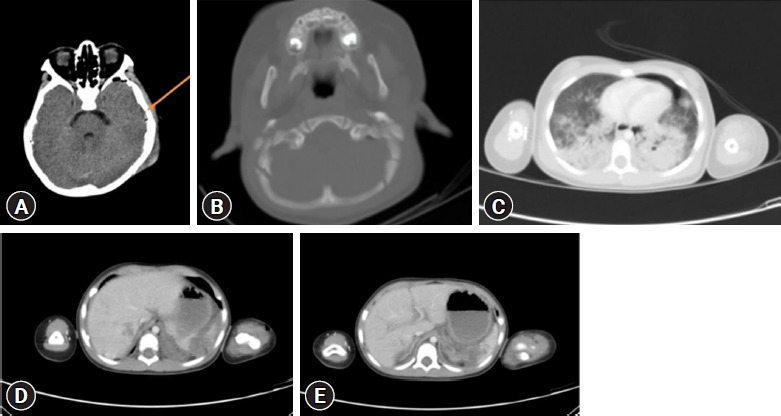

In Korea, helicopter emergency medical services (HEMS) with a physician on board were introduced in September 2011, funded by both central and regional governments. HEMS was integrated into the Korean emergency medical system to address the need for EMS in remote rural areas. The present report describes 16-month-old twins who fell from the fifth floor of an apartment building, located approximately 100 km from the nearest level I trauma center. Utilizing HEMS along with initial emergency management by an emergency physician, the patients were transported to the level I trauma center within the critical "golden hour." The children had sustained multiorgan injuries. Without intervention at the scene by an emergency physician, a fatal outcome was anticipated for both children. With the use of HEMS, one patient died, but the other survived with a good prognosis. The use of HEMS flights with an emergency physician on board may improve outcomes for pediatric patients with severe trauma in medically underserved rural areas.

Abstract Image